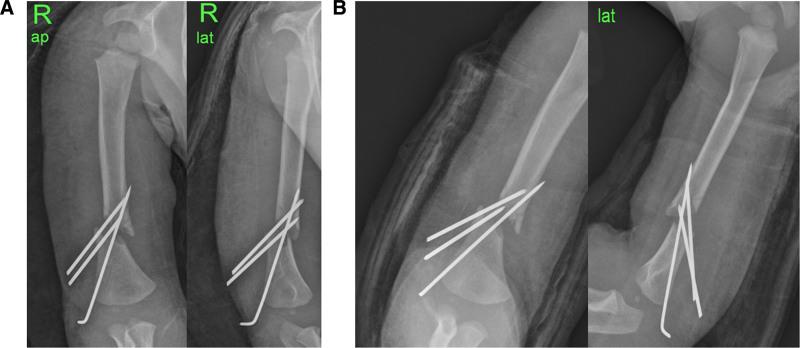

INTERVENTIONS

The authors initially attempted open reduction and internal fixation of the fracture using a Steinmann pin after radial nerve exploration, which confirmed continuity of the normal radial nerve, but fixation failed. Reduction loss and displacement progressed with pin migration the day after surgery, and revision surgery was selected. Closed reduction and intramedullary nailing using K-wires were performed on day 2 after the primary surgery.

OUTCOMES

The patient recovered his ability to extend the wrist and metacarpophalangeal joint approximately 3 weeks after surgery. At the 1-month and 6-month follow-up, the fracture had healed, and radial nerve function had recovered completely.

LESSONS

Intramedullary nailing using K-wires for metaphyseal-diaphyseal fractures of the humerus in toddlers is an effective operative treatment. Among them, high-energy open fractures accompanied by radial nerve palsy might require nerve exploration.

作者最初在探查桡神经后,尝试使用斯氏针进行骨折的切开复位内固定,确认桡神经正常连续性,但固定失败。术后第二天,随着钢针移位,复位丢失和移位进展,遂选择再次手术。在初次手术后第2天进行了闭合复位和K针髓内钉固定。

结果

术后约3周,患者恢复了伸腕和掌指关节的能力。在1个月和6个月的随访中,骨折已愈合,桡神经功能完全恢复。

经验教训

对于幼儿肱骨干骺端-骨干骨折,使用K针进行髓内钉固定是一种有效的手术治疗方法。其中,高能开放性骨折合并桡神经麻痹可能需要进行神经探查。